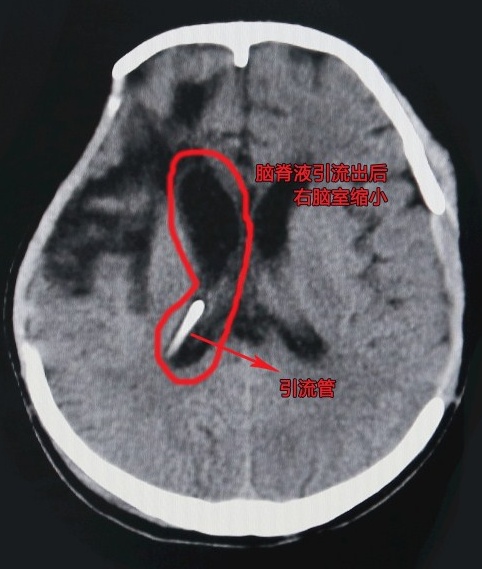

術(shù)后患者右腦室縮小,顱內(nèi)壓降低

侯主任查看病人顱腦CT后發(fā)現(xiàn),病人腦積水有增多的跡象,若不盡快手術(shù)引流,會導(dǎo)致腦室增大進而影響病人傷情恢復(fù)。征求病人家屬同意后,侯主任于11月13日下午為患者行腦室-腹腔分流術(shù)。